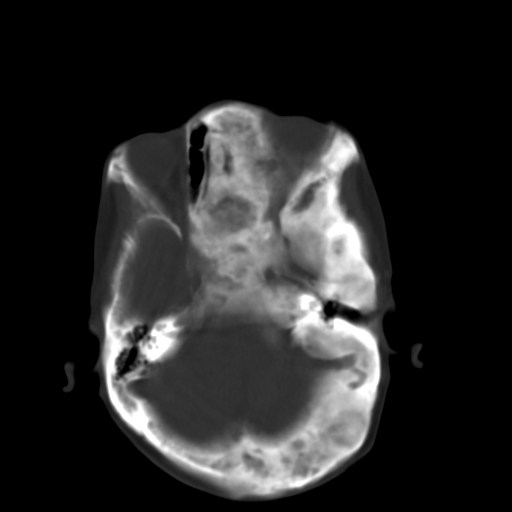

标题: CT17003:F58Y,骨纤维异常增殖征 [打印本页]

标题: CT17003:F58Y,骨纤维异常增殖征

女58y 头晕就诊

左侧额骨增厚,板障层密度增高。 支持骨纤维异常增殖症  。

符合颅骨骨纤维异常增殖症表现。